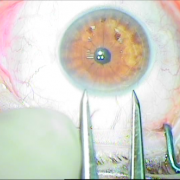

ιριδικής στήριξης

καταρράκτης με τραυματική

ρήξη οπ.περιφάκιου από

έγγχυση ANTIVGEF παράγοντα

του οπ. περιφάκιου